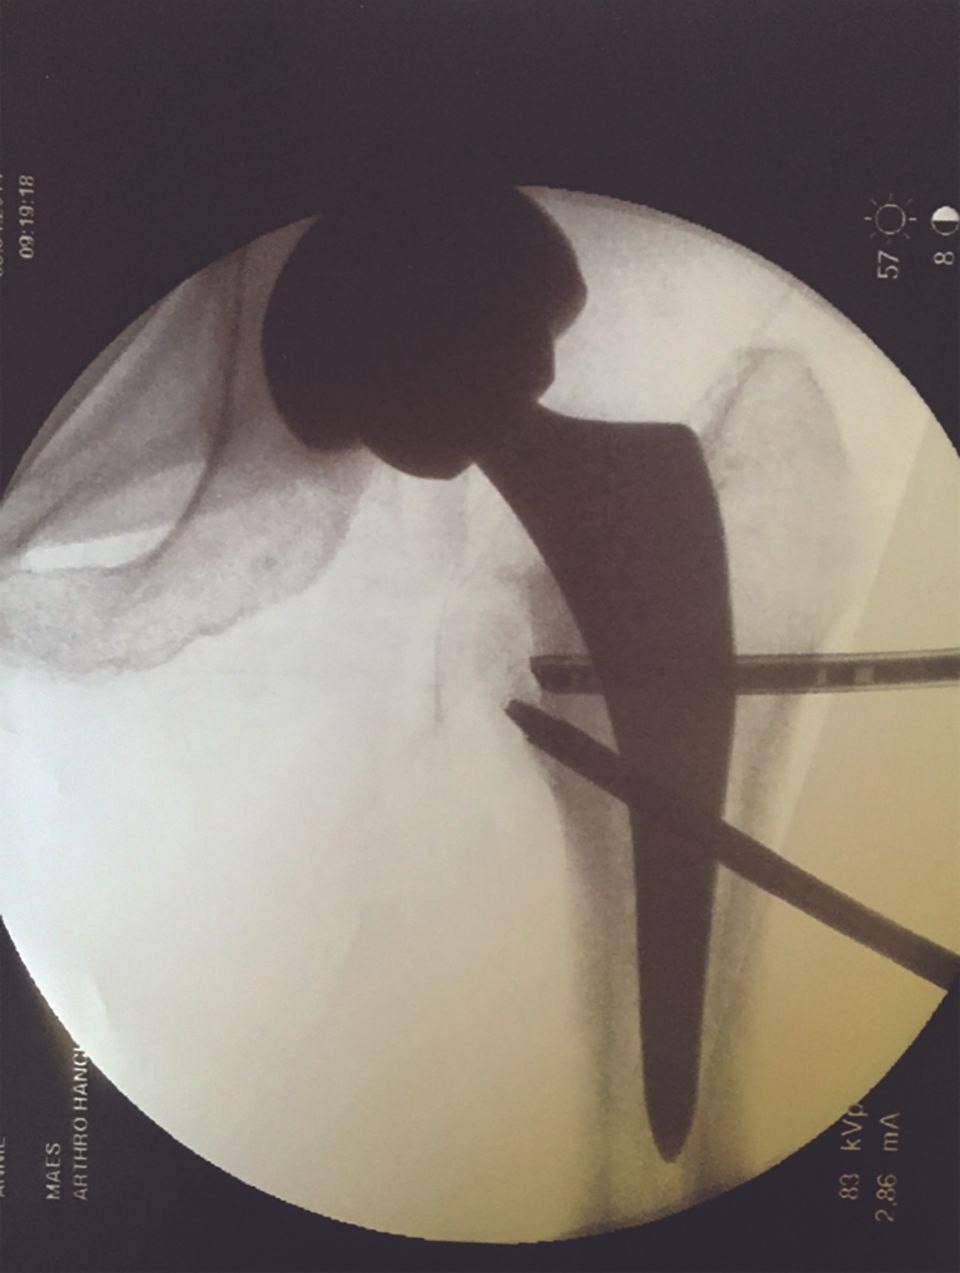

It makes it possible to view a sufficient space between the apex of the femoral head and the roof of the acetabulum to facilitate the insertion of the different trocars. The traction is deemed effective when a light-coloured crescent at least 10 mm thick appears in the coxofemoral joint (Fig. 2).

The entry point in the skin is made where the line passing over apex of the greater trochanter (perpendicular to the ASIS–patella line) intersects with the line mapping the anterior edge of the femur. This point is situated approximately 1 cm above and 1 cm in front of the greater trochanter (Fig. 3, left). Using the image intensifier, if the patella is facing up, the needle will be parallel to the floor and pointed towards the clear space in the separated joint (Fig. 3, right).